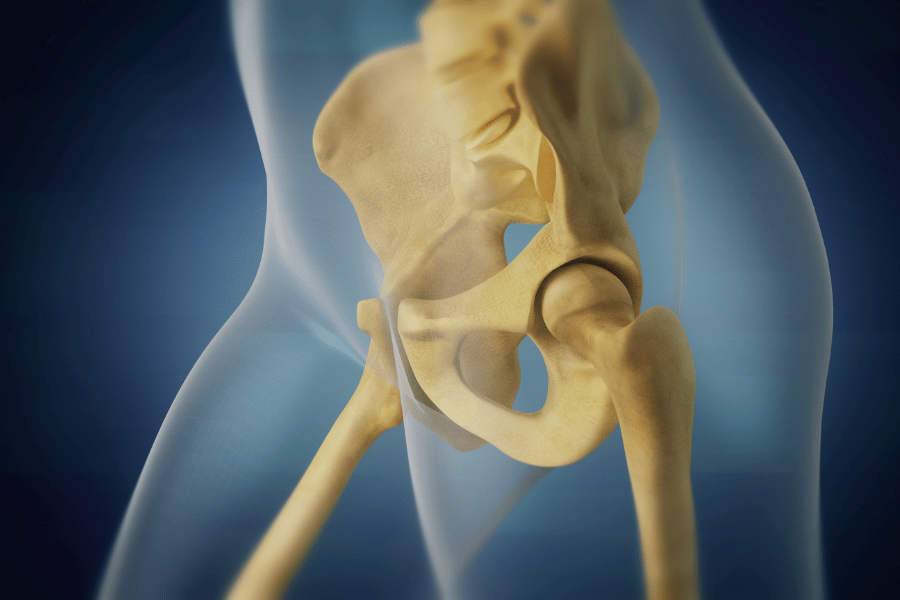

- Kolk

Kolki: nasveti in vaje za odpravljanje bolečin

Včasih so težave s kolki zelo očitne - bolečine so...

Poškodovan labrum kolka – kako ukrepati?

Do poškodbe labruma kolka običajno pride zaradi več razlogov. Glavni...Izpostavljeno